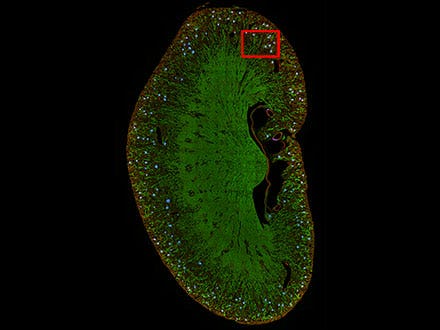

4) Segmentierung von Gewebeproben

TruAI kann auch zur Segmentierung von Gewebeproben verwendet werden. Zum Beispiel können Nierenglomeruli, die mit herkömmlichen Methoden schwer zu unterscheiden sind, mit TruAI segmentiert werden.

Abbildung 8: Vorhersage von Glomeruli-Positionen auf einem Maus-Nierenschnitt mit TruAI (blau).

Abbildung 9: TruAI erfasst und detektiert die Glomeruli-Merkmale (rechts).